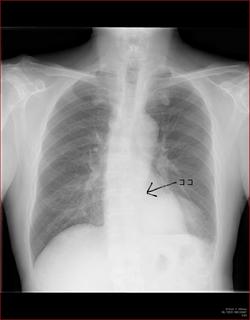

こちらを見て下さい。

わかりにくいかもしれませんが、このあたり。

気管が追いにくい、無くなっているようにも見えます。